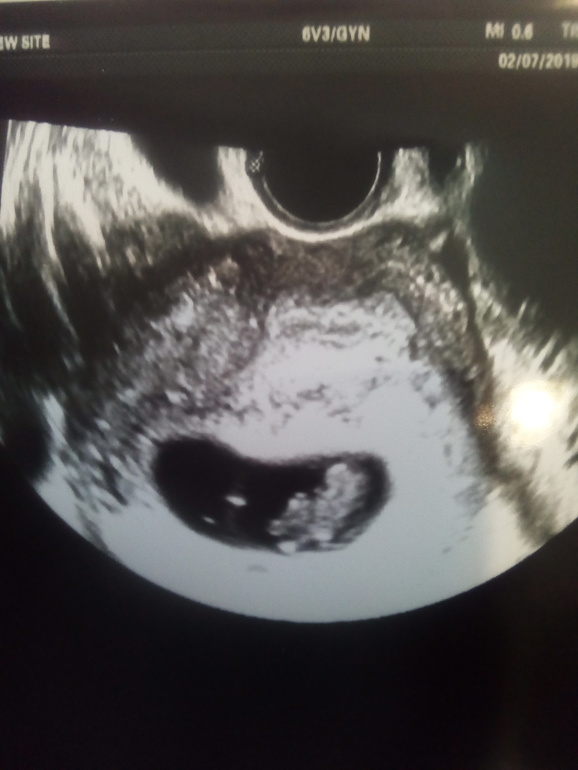

Всем привет! Это опять я! Выкладываю фото с заключением УЗИ и фото плода. Судя по его размерам. Зачатие было 12 мая в день овуляции и он точно совпадает по сроку. Или я ошибаюсь?

Не понятно как она считает срок.если по мес то срок не подходит,если эмбриональнве,то по размеру больше ставит.тк если вы точно овуляцию знаете то у вас эмбриональная 8 неделя только идет.в любом случае перепроверять надо

Да, она по плоду считала срок. По месячным говорит 9 недель

Поставили минус, но какие-то непонятные колыхания были, а что именно непонятно.

Соответствует сроку. УЗИ поставили по факту. От месячных если, то явно больше срок.

Нормальные месячные были 30 апреля. А дальше мазня вместо них

9 июля иду, сейчас на приеме была. Врач сказала, что матка на 10 недель